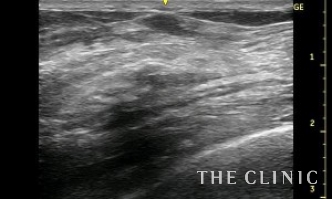

ベイザーリポによる充実性のしこり治療は被膜が残存するので5㎝以上のしこりの場合はこのようにリンパ液が貯留することがありますが、何度かエコー下に穿刺吸引することで貯留しなくなります。